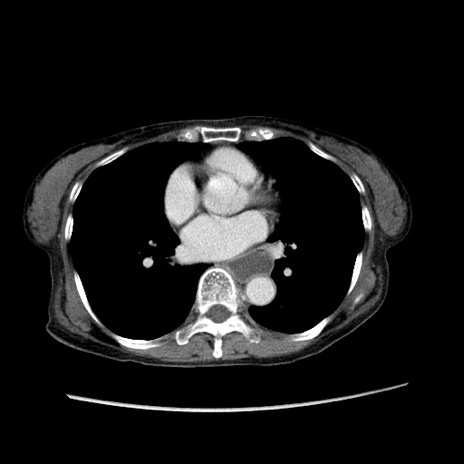

症例25(横断像)

【症例】80歳代女性

【主訴】胸のつかえ感

【現病歴】約9時間前に食後から胸のつかえた感じあり、嘔吐あり、来院。

【既往歴】胃癌(全摘)、胆摘、虫垂炎

【身体所見】心窩部に圧痛あり、反跳痛なし。

【データ】WBC 5700、CRP 0.05